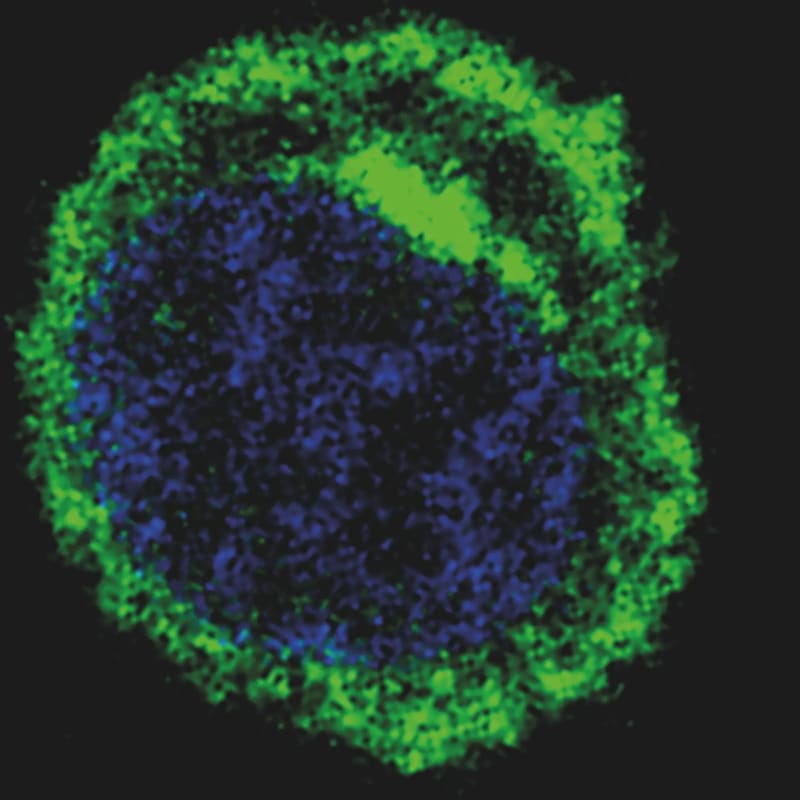

A 15-year study reveals that 42% of advanced follicular lymphoma patients can now be considered cured after standard treatment, challenging decades of medical belief that this cancer was incurable. Relapse rates dropped from nearly 7% in the first five years to just 0.6% after 15 years.